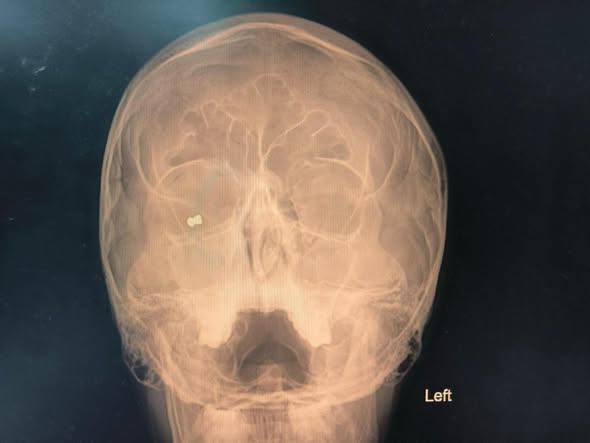

Студент от Испания, обучаващ се по програма „Еразъм“ в Букурещ, е бил прострелян с въздушна пушка пред нощен клуб в центъра на София на 24 октомври вечерта. При спешния преглед офталмолозите установили метално чуждо тяло в орбитата на дясното око и разкъсна рана на клепача, характерна за прострелване.

След извършените изследвания и подготовка екипът на доц. Яни Здравков провел спешна операция, при която успешно е била извадена сачма от въздушна (газова) пушка. Интервенцията е преминала без усложнения, а състоянието на пациента вече е стабилно.